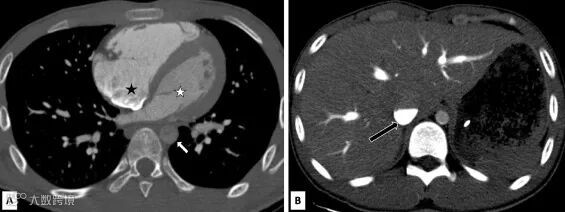

在CT扫描的动脉期,扫描技师发现图像右心室、下腔静脉和肝静脉造影剂汇集呈现高密度,相比之下,左心室和降主动脉的造影剂注入极少(图1)。

pic .1 该患者的CT增强图像横断面

(A) 增强CT图像显示造影剂在右心房和右心室积聚(黑星)。与右心室相比,左心室(白色星形)和降主动脉(白色箭头)中仅有少量造影剂。

(B) 动脉期显示造影剂在肝静脉中汇集,并在下腔静脉中分层(黑色箭头)。